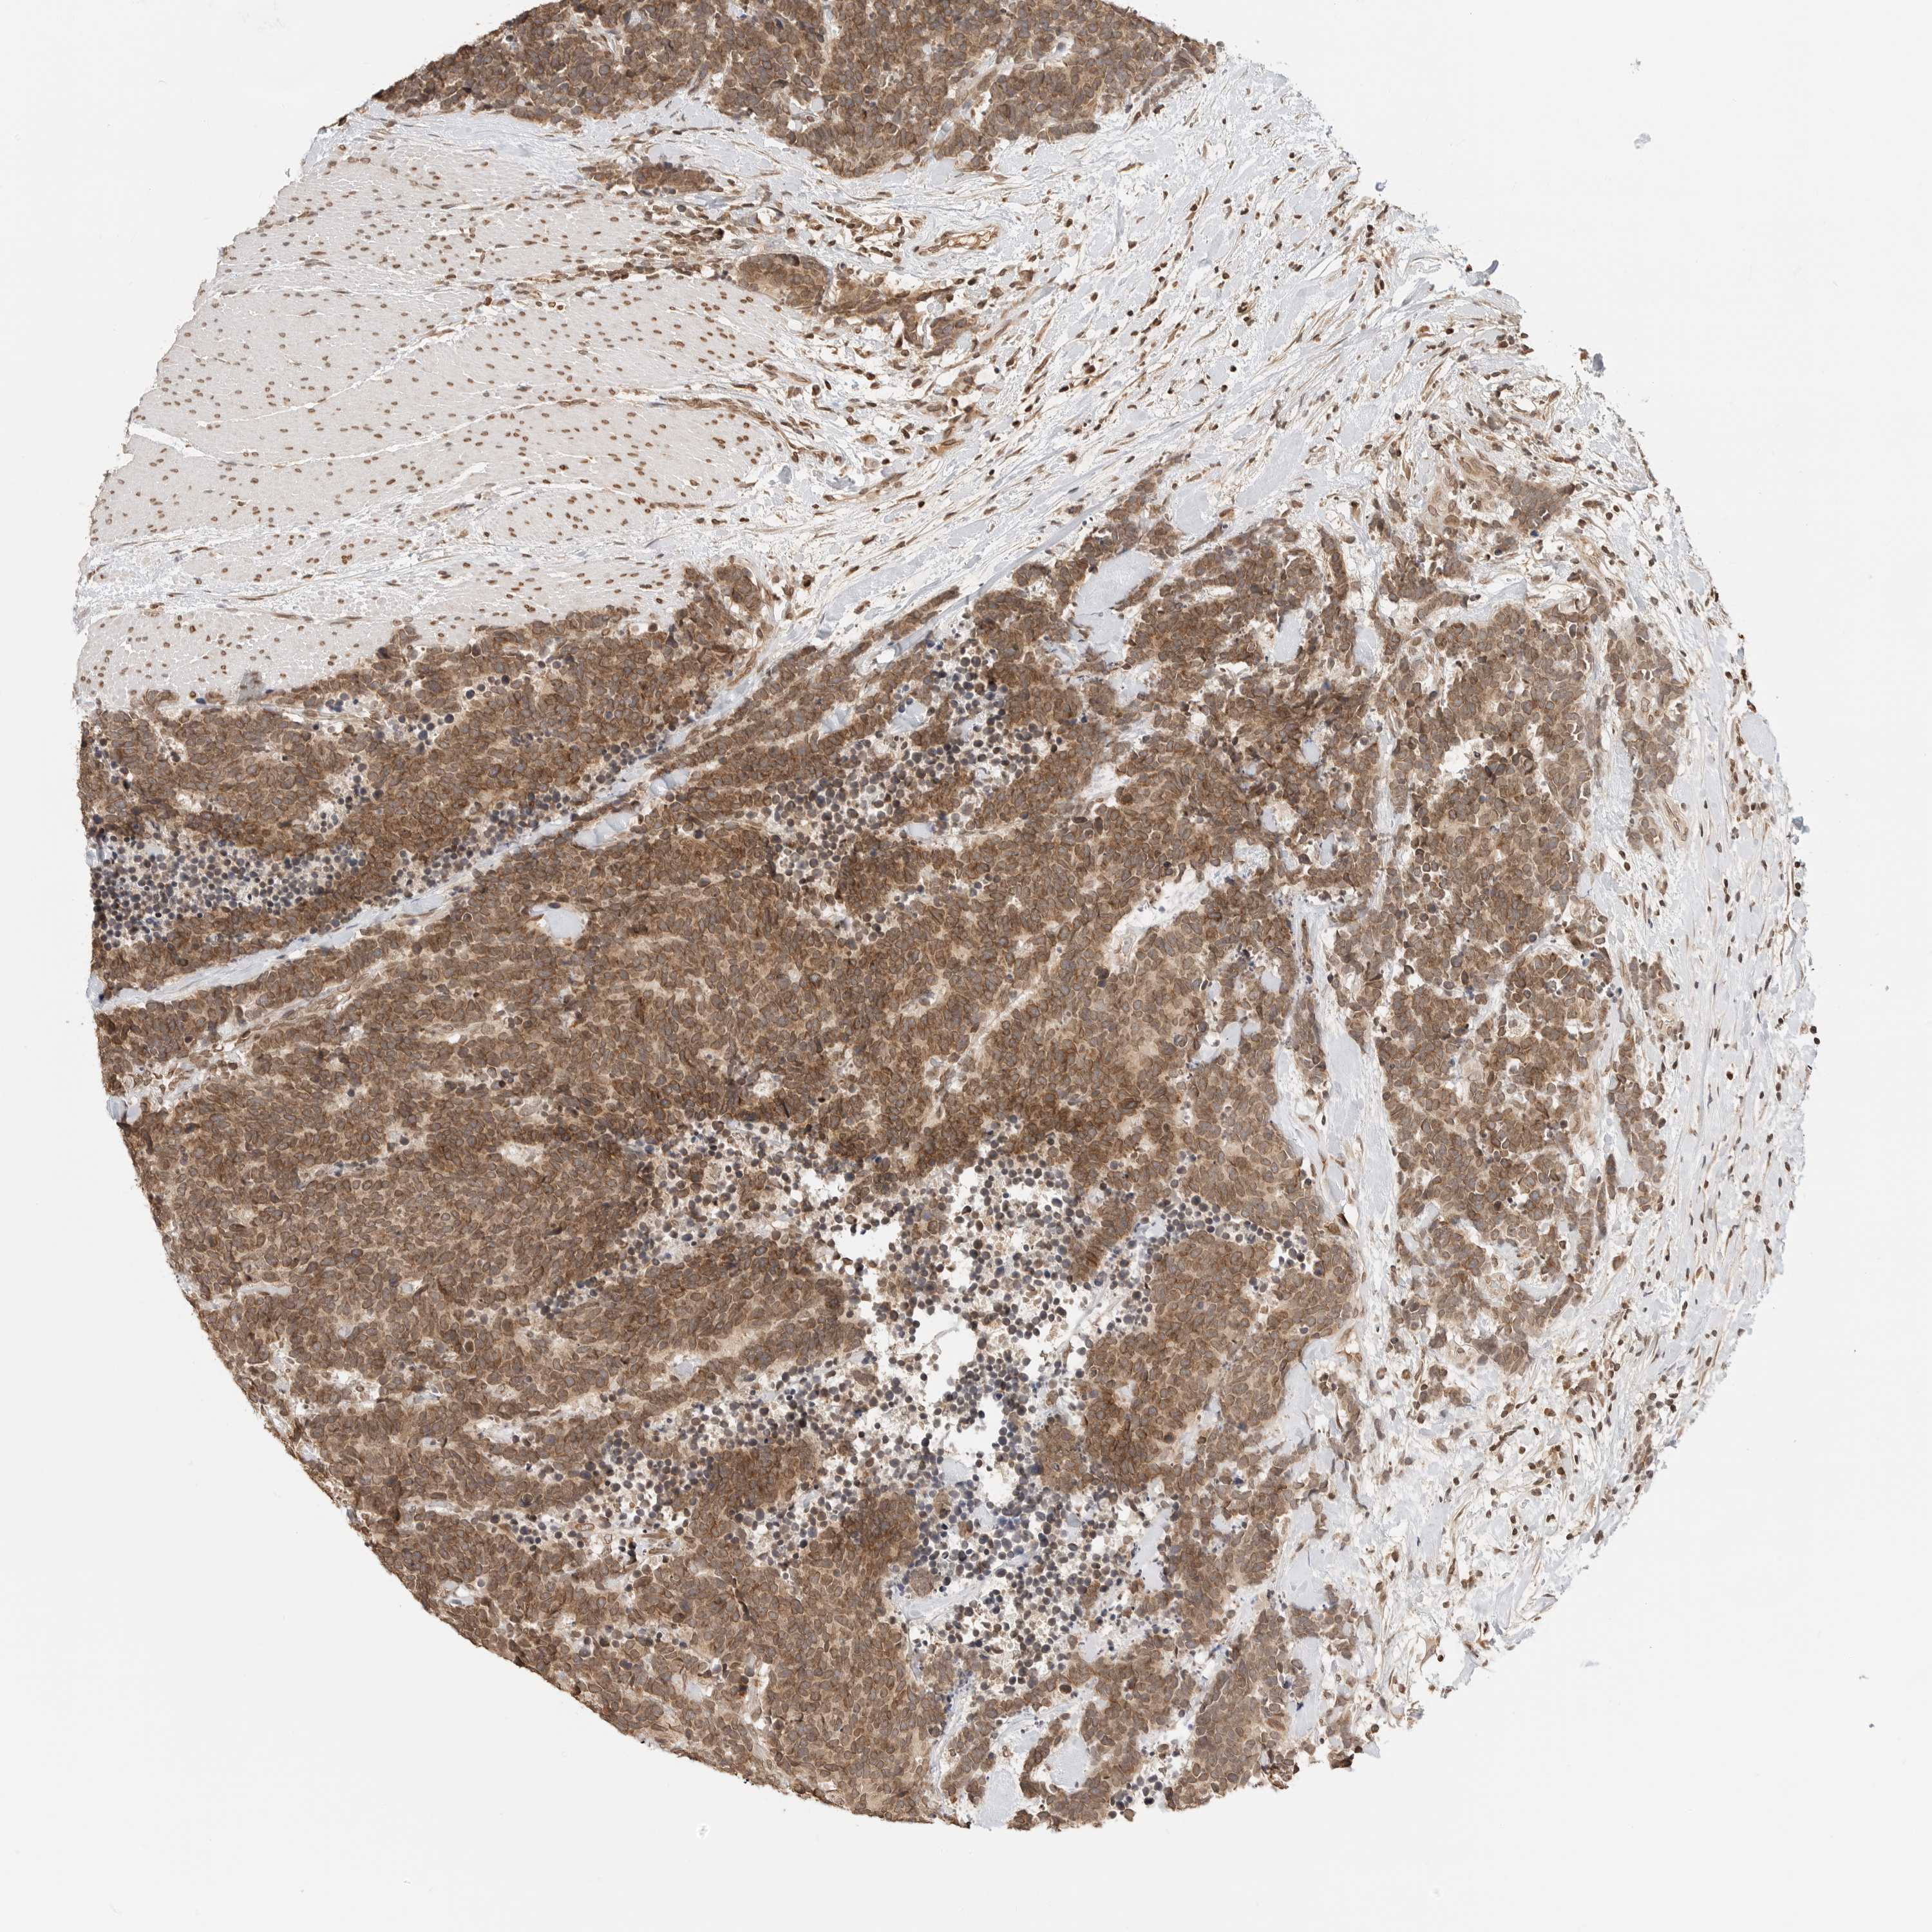

CARCINOID - Protein expressioni

A mouse-over function shows sample information and annotation data. Click on an image to view it in a full screen mode. Samples can be filtered based on level of antibody staining by selecting one or several of the following categories: high, medium, low and not detected. The assay and annotation is described here.

Antibody stainingi

Antibody staining in the annotated cell types in the current human tissue is reported as not detected, low, medium, or high, based on conventional immunohistochemistry profiling in selected tissues. This score is based on the combination of the staining intensity and fraction of stained cells.

Each image is clickable and will lead to virtual microscopy that enables deeper exploration of all samples and also displays staining intensity scores, fraction scores and subcellular localization as well as patient and tissue information for each sample.

Antibody HPA006721

Staining

High

Intensity

Strong

Quantity

>75%

Location

Nuclear

Carcinoid, malignant, NOS